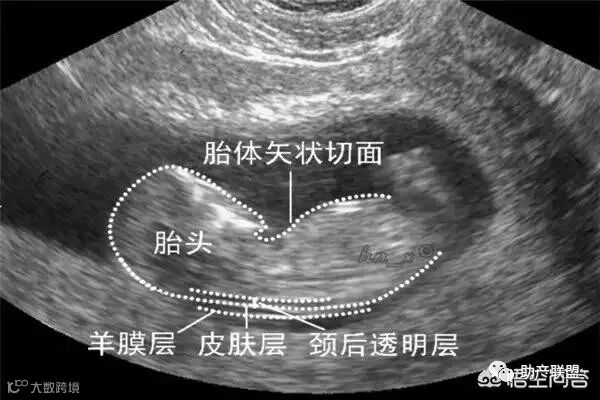

2.检查时间:孕11~13周+6,过了14周胎儿颈后透明带就会消失,被淋巴组织吸收。所以最晚不能晚于13周+6。

5.检查项目:主要通过胎儿颈后透明带的厚度来排查胎儿是否染色体异常或先天性心脏病等畸形。